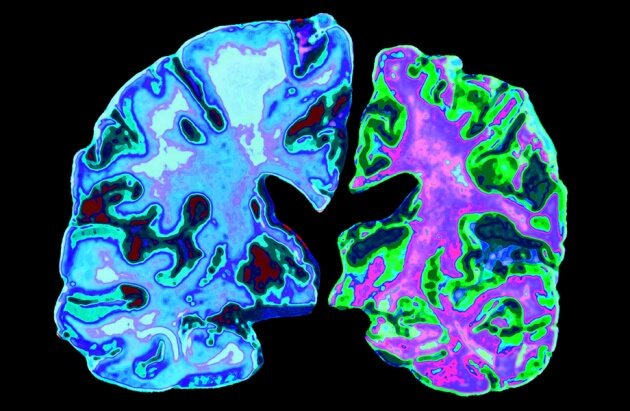

A plaque-causing substance may be the brain fighting the real cause of Alzheimer’s: infections by pathogens | Kenneth Shinozuka